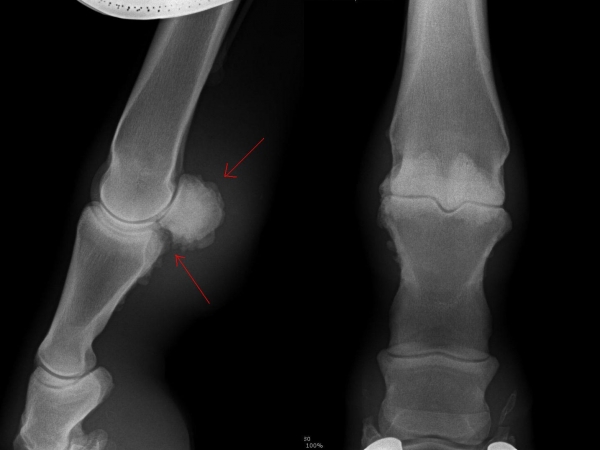

Čip ve spěnkovém kloubu na pánevní končetině

Ankylóza spěnkovýho kloubu

rentgenologické vyšetření

ohebové zkoušky

Těžká artróza ve spěnkovém kloubu

Fragment na spěnkové kosti